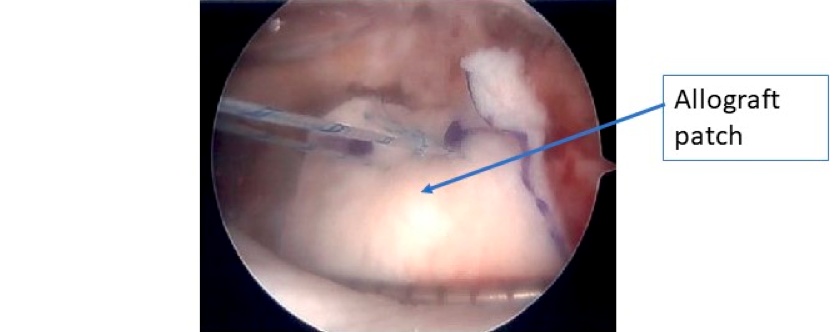

Arthroscopic revision rotator cuff repair

Arthroscopic images of a revision rotator cuff repair using patch augmentation to help with healing.

D) Final image after graft has been tied down securely over the traditional rotator cuff repair.